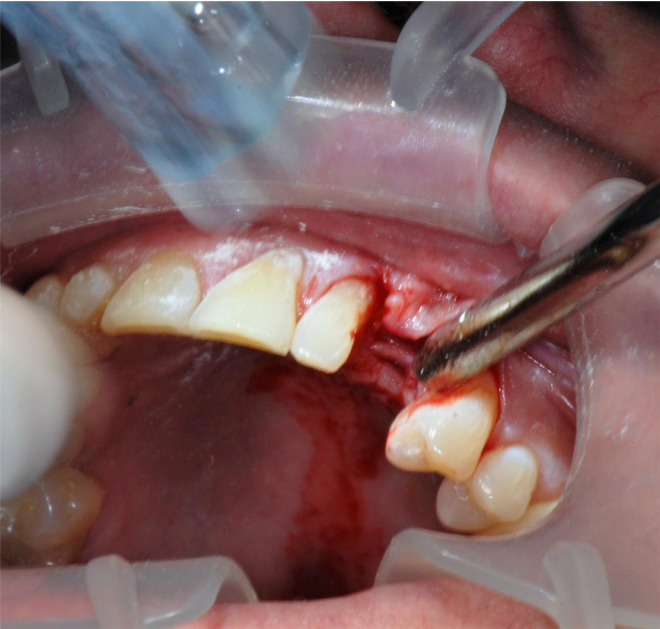

These data were used to fabricate the surgical guide and a temporary. Figure 9 shows the implant in place digitally. All the data and models were taken into account before surgery. The clinician received a 3D-printed model with the tooth extracted, a guide (Figure 10), and a healing cap and temporary (Figure 11). The latter two were required for initial stability of the implant to immediately provisionalize. The "bail-out clause" is the healing cap because if the implant cannot be immediately loaded, the healing cap can be placed instead. For this case, the patient's tooth was extracted and bone had been grafted several months previously. Figure 12 shows the patient's previous tooth bonded into place. The flap was laid (Figure 13) and the surgeon was given a set of instructions that come with every guided case.

Fig 13. The location was prepared by laying a flap.

Figure 13